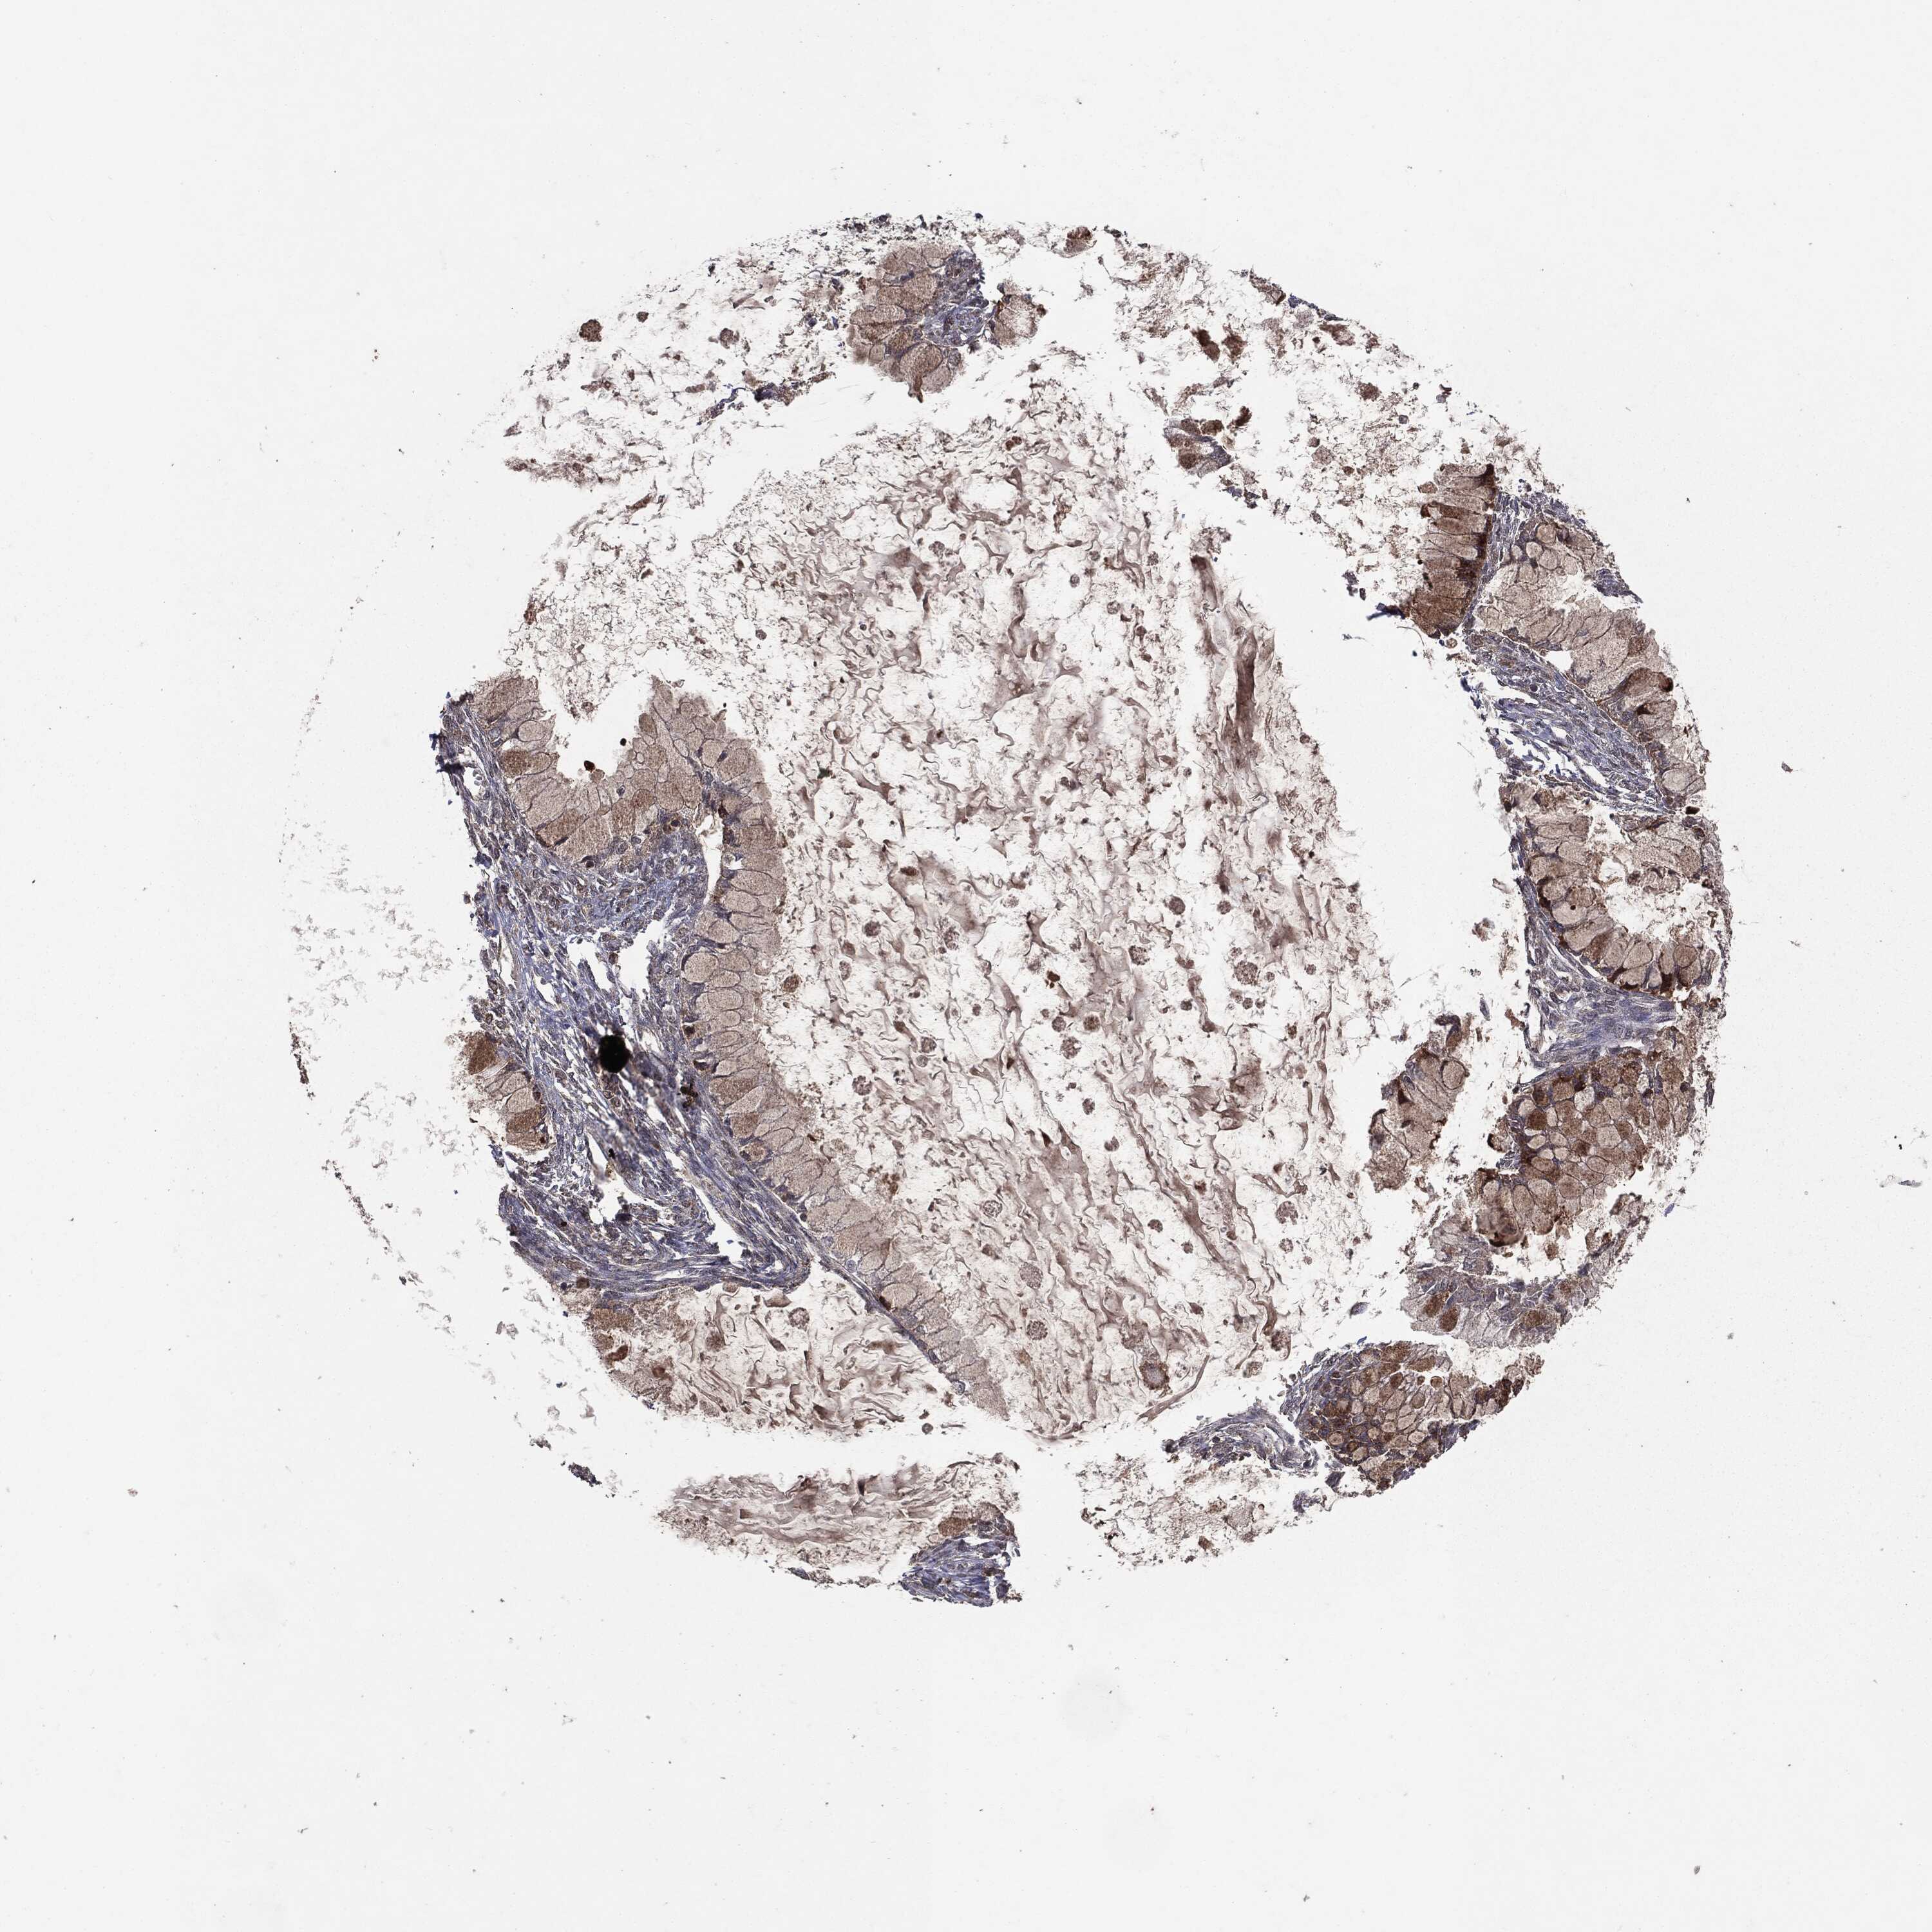

OVARIAN CANCER - Protein expressioni

A mouse-over function shows sample information and annotation data. Click on an image to view it in a full screen mode. Samples can be filtered based on level of antibody staining by selecting one or several of the following categories: high, medium, low and not detected. The assay and annotation is described here.

Note that samples used for immunohistochemistry by the Human Protein Atlas do not correspond to samples in the TCGA dataset.

Antibody stainingi

Antibody staining in the annotated cell types in the current human tissue is reported as not detected, low, medium, or high, based on conventional immunohistochemistry profiling in selected tissues. This score is based on the combination of the staining intensity and fraction of stained cells.

Each image is clickable and will lead to virtual microscopy that enables deeper exploration of all samples and also displays staining intensity scores, fraction scores and subcellular localization as well as patient and tissue information for each sample.

CAB069425